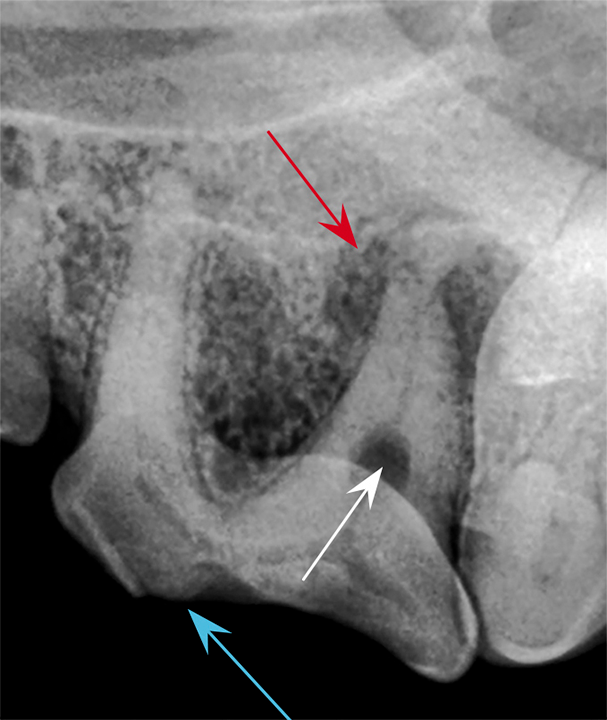

Periapical lucency develops secondary to bone loss around the tooth root caused by endodontic, neoplastic, or periodontal disease. In this dog, periapical lucency of the maxillary first and second molars (red arrows) developed secondary to periodontal disease. Periapical lucency secondary to endodontic disease (caused by exposure of the pulp from a slab fracture [blue arrow]) is also present surrounding the roots of the right maxillary fourth premolar (white arrow).

Observation of marked mobility of the molars would be expected on anesthetized examination. In this dog, the maxillary fourth premolar would likely not be mobile, as there is still bone surrounding the root apices. Extraction of the maxillary fourth premolar and first and second molars is indicated.